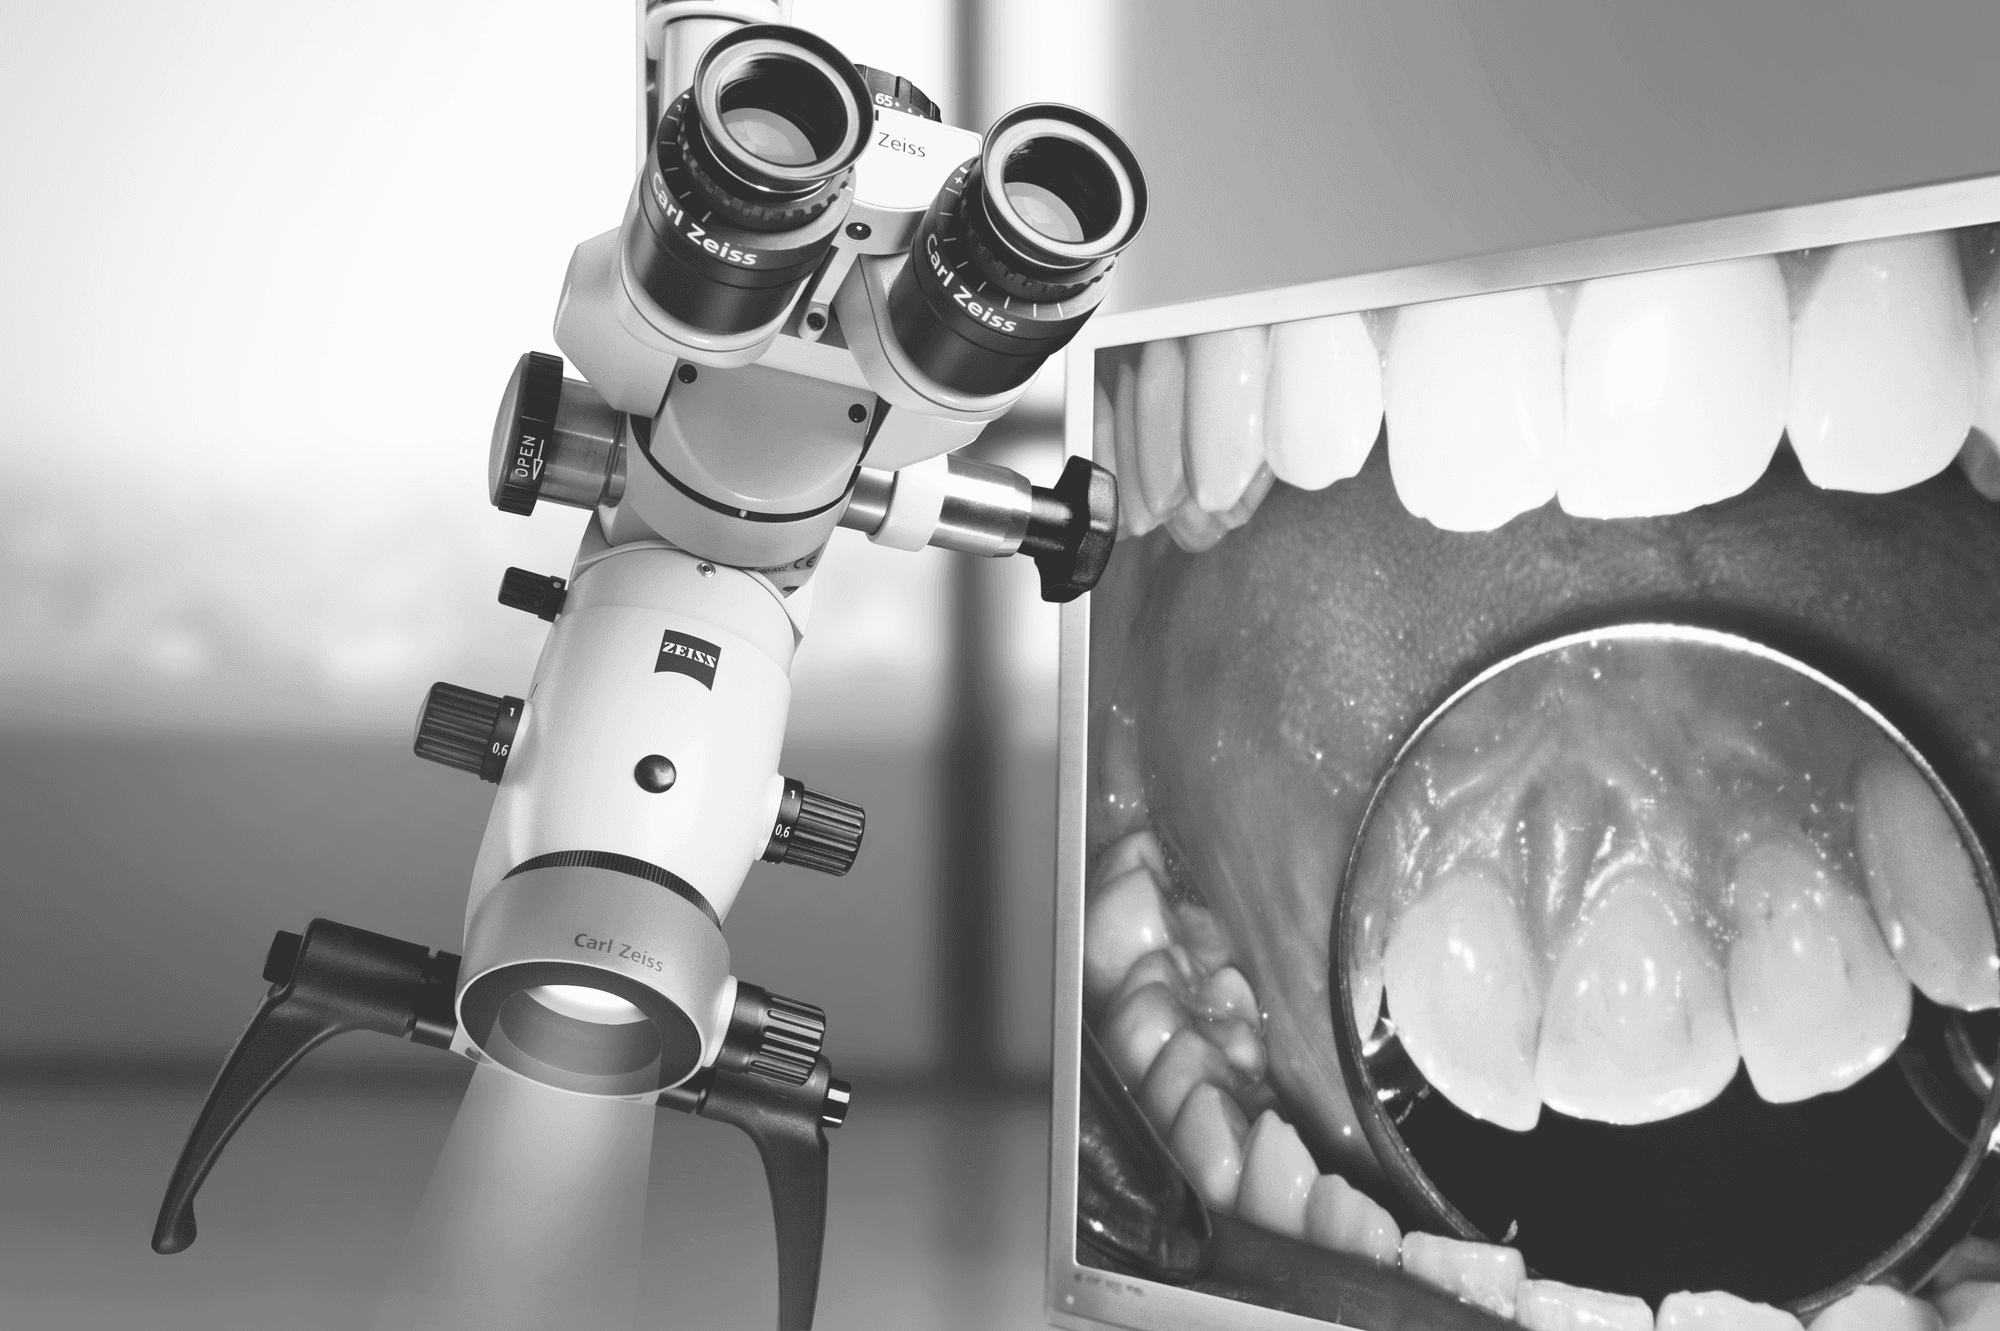

미세현미경 신경치료

자연치아를 끝까지 지키는 정밀 솔루션

신경치료가 필요한 순간

치아 속 신경(치수)이 충치·균 감염·외상으로 손상되면 극심한 통증이 시작됩니다. 신경치료(근관치료)는 이 감염된 신경과 혈관을 제거‧소독해 발치 대신 치아를 보존하는 마지막 방법입니다.

왜 ‘미세 현미경’이 중요한가요?

육안의 한계를 넘는 최대 25배 확대 시야로, 뿌리 끝까지 환히 들여다보며 치료합니다.

정밀 진단 – 눈에 보이지 않던 잔존 감염·미세 균열까지 포착

오차 없는 치료 – 머리카락 굵기보다 가는 세근관도 깔끔히 청소·형성

재발 차단 – 감염 부위를 완전히 제거하고 밀폐해 실패율을 대폭 감소

미세 현미경 신경치료의 핵심 장점

높은 성공률 : ㎛ 단위 정밀 시술로 재치료 확률 최소화

치료 시간 단축 : 정확도가 높아 불필요한 내원·재시술을 줄임

통증·부작용 감소 : 손상 조직만 선택적으로 제거해 회복이 빠름

자연치아 보존 극대화 : 뿌리 구조를 최대한 보존해 수명 연장

자연치아는 인공치아보다 더 소중합니다.

미세 현미경 신경치료로 통증을 잡고, 치아를 끝까지 지켜 드립니다.